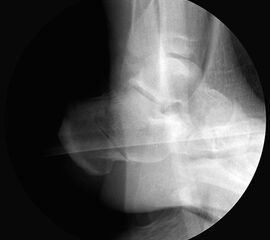

Bei Rückfussfehlstellungen ist meist eine knöcherne Korrektur des Kalkaneus indiziert. Dabei wird das Fersenbein im Bereich des Tuber calcanei durchtrennt und der Achillessehnenansatz nach medial oder lateral geschoben. Zusätzlich ist eine Rotation des Tuber möglich, wodurch sich der Korrektureffekt noch verstärkt. Durch die Wahl der Osteotomieebene kann die Verscheibung mit einer Verlängerung oder Verkürzung des Fersenbeins kombiniert werden. Die Osteosynthese erfolgt typischerweise durch perkutan eingebrachte Schrauben.

Röntgenaufnahmen des Fußes d.p., streng seitlich und schräg unter Belastung. Saltzmann Aufnahme zur Beurteilung der Rückfussachse.

Operationsplanung anhand der Röntgenaufnahmen unter Beachtung wichtiger radiologischer Landmarks wie Rückfussachse, Metatarsale I – Talushals-Achse im dp und lateralen Strahlengang (Abbildung 1 und 2).

Kanülierte Schrauben bis 80 mm Länge.

Kirschnerdraht mit 2,0 mm zur Verschiebung des Tuber calcanei.